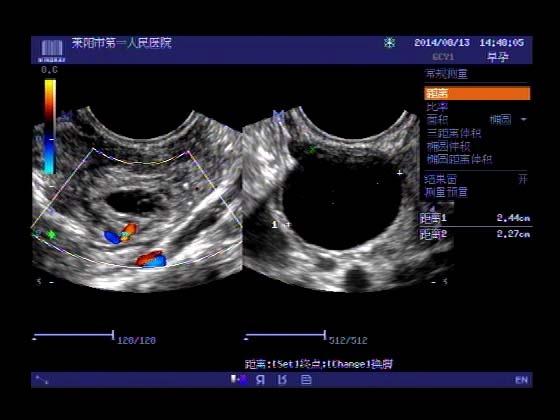

超声入门贴341:宫外孕(阴超的魅力)

女,32岁,停经15天,

一周前在上极医院检查:化验尿HCG阳性,血HCG400多,超声检查问见明显孕囊,让随访。

很典型,图像不错,阴超的优势!!

看见卵黄囊啦~孕囊型的吧?

还能看到卵黄囊,真不错